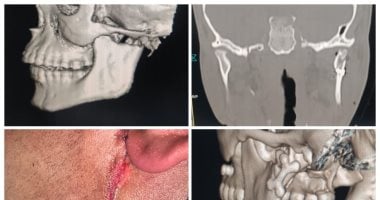

وتلقى القسم حالة معقدة لكسر في الفك السفلي مع تهتك بالأنسجة الرخوة، استدعت تدخّلًا جراحيًا عاجلًا ودقيقًا للحفاظ على الوظيفة والشكل في الوقت نفسه. وبعد التقييم الإكلينيكي والأشعات ثلاثية الأبعاد، تم وضع خطة علاجية دقيقة شملت إعادة العظام إلى وضعها التشريحي الصحيح، الحفاظ على الإطباق السليم، تقليل الأثر التجميلي قدر الإمكان، وحماية الأعصاب والأنسجة الحيوية.

وشملت العملية دخولًا جراحيًا محسوبًا، وردًا دقيقًا لقطع العظام، وتثبيتًا مستقرًا يضمن الالتئام الوظيفي والتجميلي، مع غلق دقيق للأنسجة الرخوة. وأسفرت العملية عن استقرار الحالة واستعادة شكل ووظيفة الفك، مع متابعة آمنة لمسار التعافي.

حالة معقدة لكسر في الفك السفلي